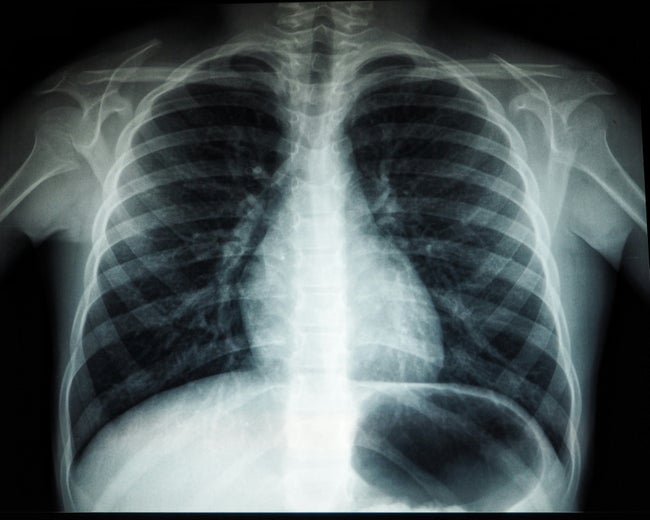

マレーシア保健省の指針に基づく調査により、ジョホール州ポンティアン地区の小学校で男子児童が結核に感染していることが確認された。同州内では、先に集団感染が報告されたコタティンギ地区以外で初の感染確認となる。

ポンティアン地区保健局は、陽性が判明した児童の同じクラスの児童や濃厚接触者を特定し、保健クリニックでの健康診断を受けるよう指示した。検査は保健省のガイドラインに沿って実施される予定だという。

なお、先週にはコタティンギ地域で結核のクラスターが発生し、保健省による濃厚接触調査の結果、複数の感染者が確認されているが、現状は治療を受けながら状況は管理下にあると報告されている。